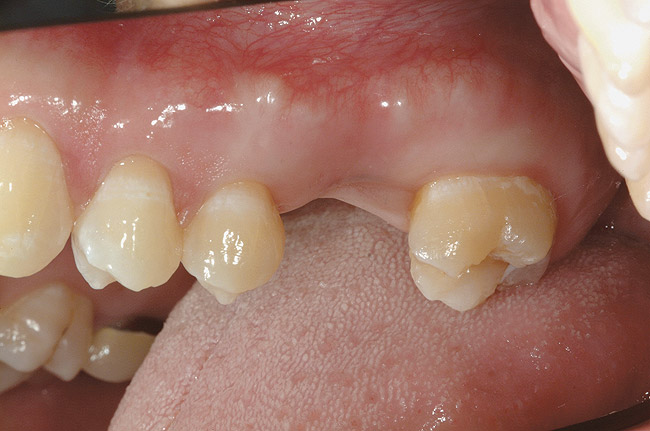

Figure 12  Proper gingival contours following placement of the implants and subsequent hard-tissue graft.

Figure 12